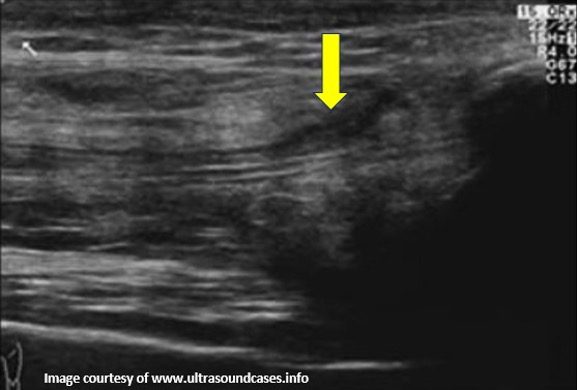

Figure 4. B-mode image showing rupture of superficial part of the quadriceps tendon. This was not an anisotropy artifact. The hypoechoic lesion did not disappear by changing the angulation of the transducer to make the ultrasound beam perpendicular to the tendon fibers. Always correlate clinically and compare with the normal side.

Figure 5. B-mode longitudinal image showing hypoechoic quadriceps tendon tendinopathy. The hypoechoic areas did not disappear even by proper angulation of the transducer to eliminate potential anisotropy artifact. Image courtesy of www.ultrasoundcases.info